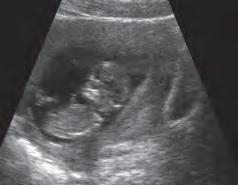

17 a-20 a settimana L’accrescimento del feto rallenta nuovamente e durante tale periodo l’aumento di peso è scarso. Anche i segmenti degli arti inferiori hanno raggiunto le loro proporzioni definitive (C). Le ghiandole sebacee secernono una sostanza grassa e biancastra, la vernice caseosa, che protegge la cute del feto dalla macerazione causata dal liquido amniotico. Si sviluppano i capelli e le sopracciglia. In tale periodo la madre percepisce per la prima volta i movimento del feto ed è consigliabile effettuare un esame ecografico di routine (D).

D Ecografia C Feto, 20a settimana